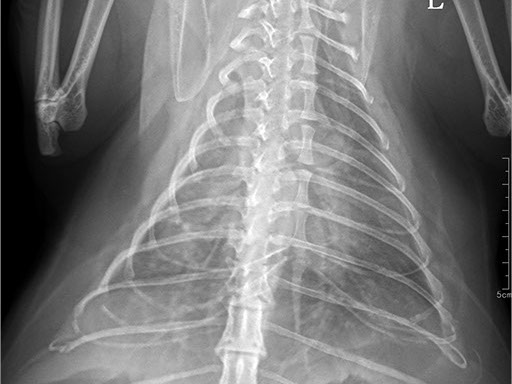

Коллиматорный прицел формирует пучок рентгеновского излучения на участок исследования. Проходя через ткани тела, излучение попадает на плоскопанельный цифровой детектор, который, в свою очередь, передает сигналы на компьютер.

В считанные секунды полученные данные обрабатываются компьютером посредством установленной на него программы визуализации, и сформированное клиническое изображение выводится на монитор лаборанта.

Клинические изображения (снимки) можно напечатать на принтере, сохранить в архиве или отправить по сети коллегам для оперативного консилиума.